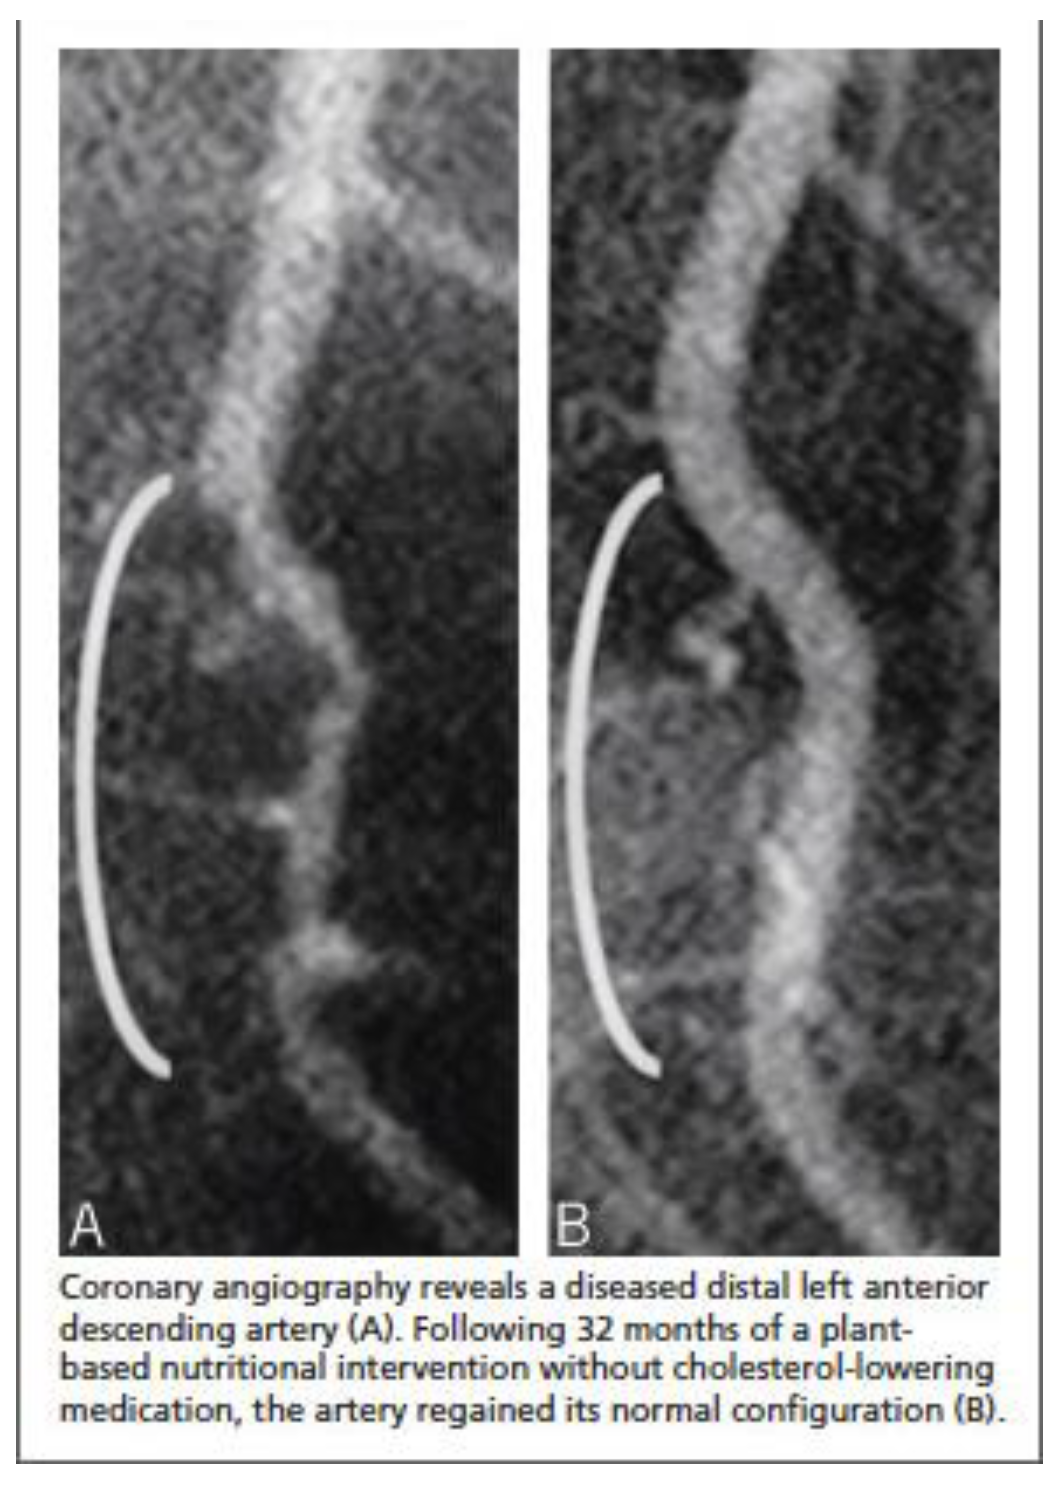

- Esselstyn CB Jr, Gendy G, Doyle J, et al. A way to reverse CAD? J Fam Pract. 2014 Jul;63(7):356-364b. PMID: 25198208.